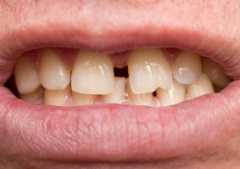

部分矯正とインプラントを組み合わせた治療例

1−5.部分矯正とセラミックで期間を短縮できるハイブリット矯正

歯を失っている部分や被せてある歯を利用して、部分矯正とセラミック治療を一緒に行う方法です。歯の移動距離を小さくすることによって歯や歯茎へのダメージを少なくします。またセラミック治療を行うことで噛み合わせを治すこともできます。歯や歯茎の負担が軽いために大人の方には特におすすめの治療法です。